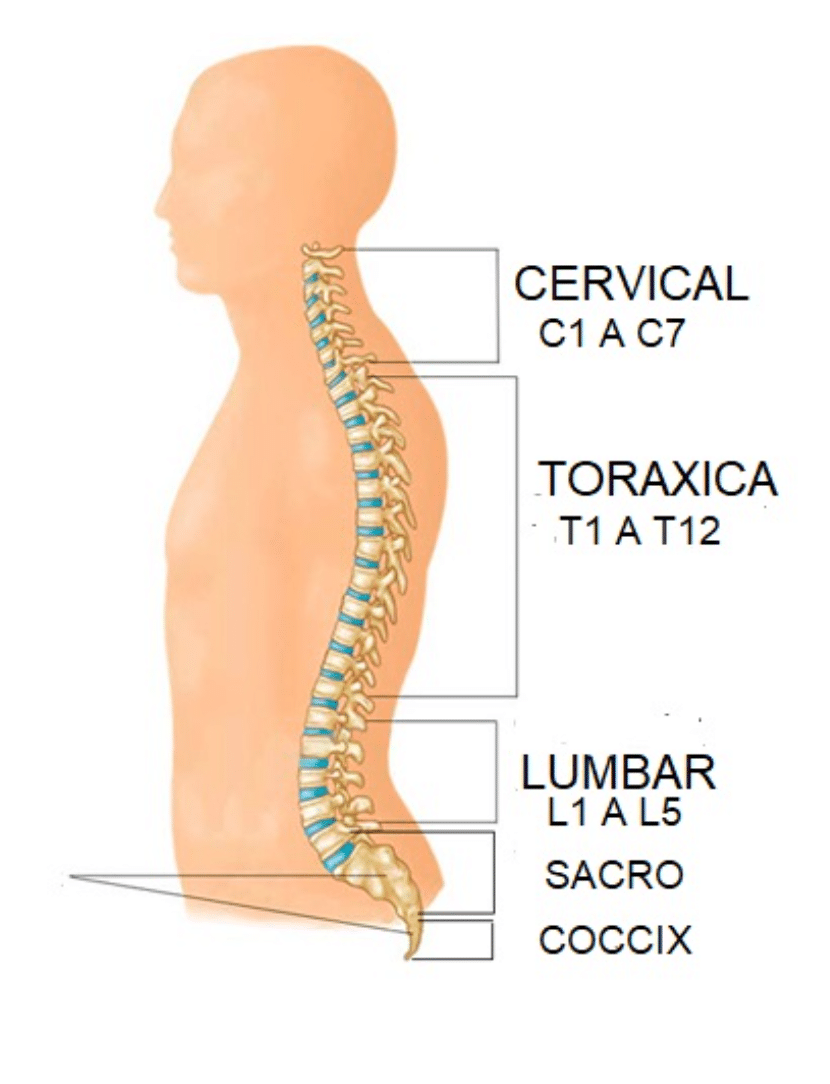

La cirugía de columna es una rama altamente especializada enfocada en el tratamiento de patologías que afectan la estabilidad, movilidad y funcionalidad de la columna vertebral, incluyendo hernias discales, estenosis espinal y enfermedades degenerativas.